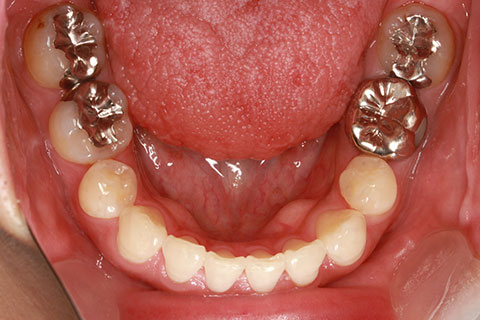

フルリンガル矯正2:上下の歯を舌側矯正で治療(矯正期間18ヶ月)

- 年齢・性別

- 42歳男性

- 治療期間

- 1年6ヶ月

- 抜歯

- なし

- 治療費

- 120万円(税込み)

- 備考

- マルチブラケットを用いた矯正治療

- 治療内容

- 反対咬合をフルリンガル矯正治療にて改善

- 施術の副作用(リスク)

- 表側矯正と比較して、歯根の角度を確立する「トルク」の力がかかりにくい。